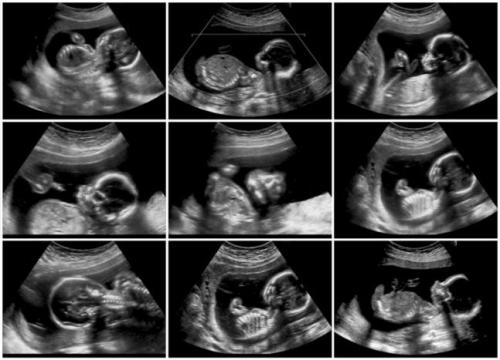

Pemeriksaan kehamilan dengan alat USG akan menjadi layanan primer di Puskesmas.

Pemeriksaan kehamilan dengan alat USG akan menjadi layanan primer di Puskesmas.  (Foto: MNC Media)

IDXChannel - Pemeriksaan kehamilan dengan alat USG akan menjadi layanan primer di Puskesmas. Upaya ini akan membantu masyarakat yang selama ini sulit menjangkau pelayanan USG dan tentunya berdampak pada kualitas ibu dan bayi yang akan dilahirkan.

Kasus kematian ibu hamil yang masih tinggi menjadi landasan utama pelayanan USG di Puskesmas ini akan dimasifkan. Pelayanan USG diharapkan akan membaca status kesehatan dan mendeteksi lebih awal jika ada kemungkinan masalah selama proses kehamilan dan dengan begitu menurunkan risiko kematian ibu hamil.